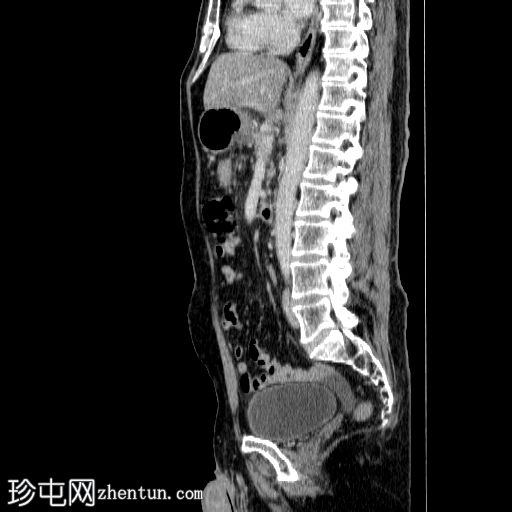

3.jpg

矢状面

非造影

胰体尾弥漫性增大,特征为胰腺实质低强化,无明显坏死区域。

该病灶与以下表现相关:

胰周筋膜平面边界不清的污迹,无明显壁形成、气室、固体碎片或血液产物。

病变横向延伸至左前肾旁间隙,伴有Gerota筋膜增厚。

病变向下延伸至盆腔。

无肠系膜或脾脏血管阻塞的证据。

未见导管扩张或钙化。